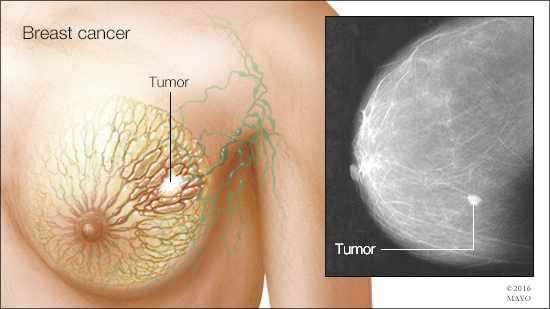

废物利用!新方法使乳腺癌诊断更精准

一项发表在《Molecular Oncology》上的新研究表明对乳腺癌常规检测剩下的组织进行蛋白质和RNA检测可能会使检测结果更准确。

通过使用细针抽吸25名乳腺癌病人和33名良性肿瘤病人的组织样品,研究人员发现通过蛋白质和RNA分析竟然可以完全将所有恶性肿瘤病人和良性病人区分开。

这项研究表明除了提供结论性诊断信息之外,通过微创技术对乳腺癌进行分型很重要,这样有助于决定每个病人最适合的疗法、监控疾病进程以及对治疗的反应。